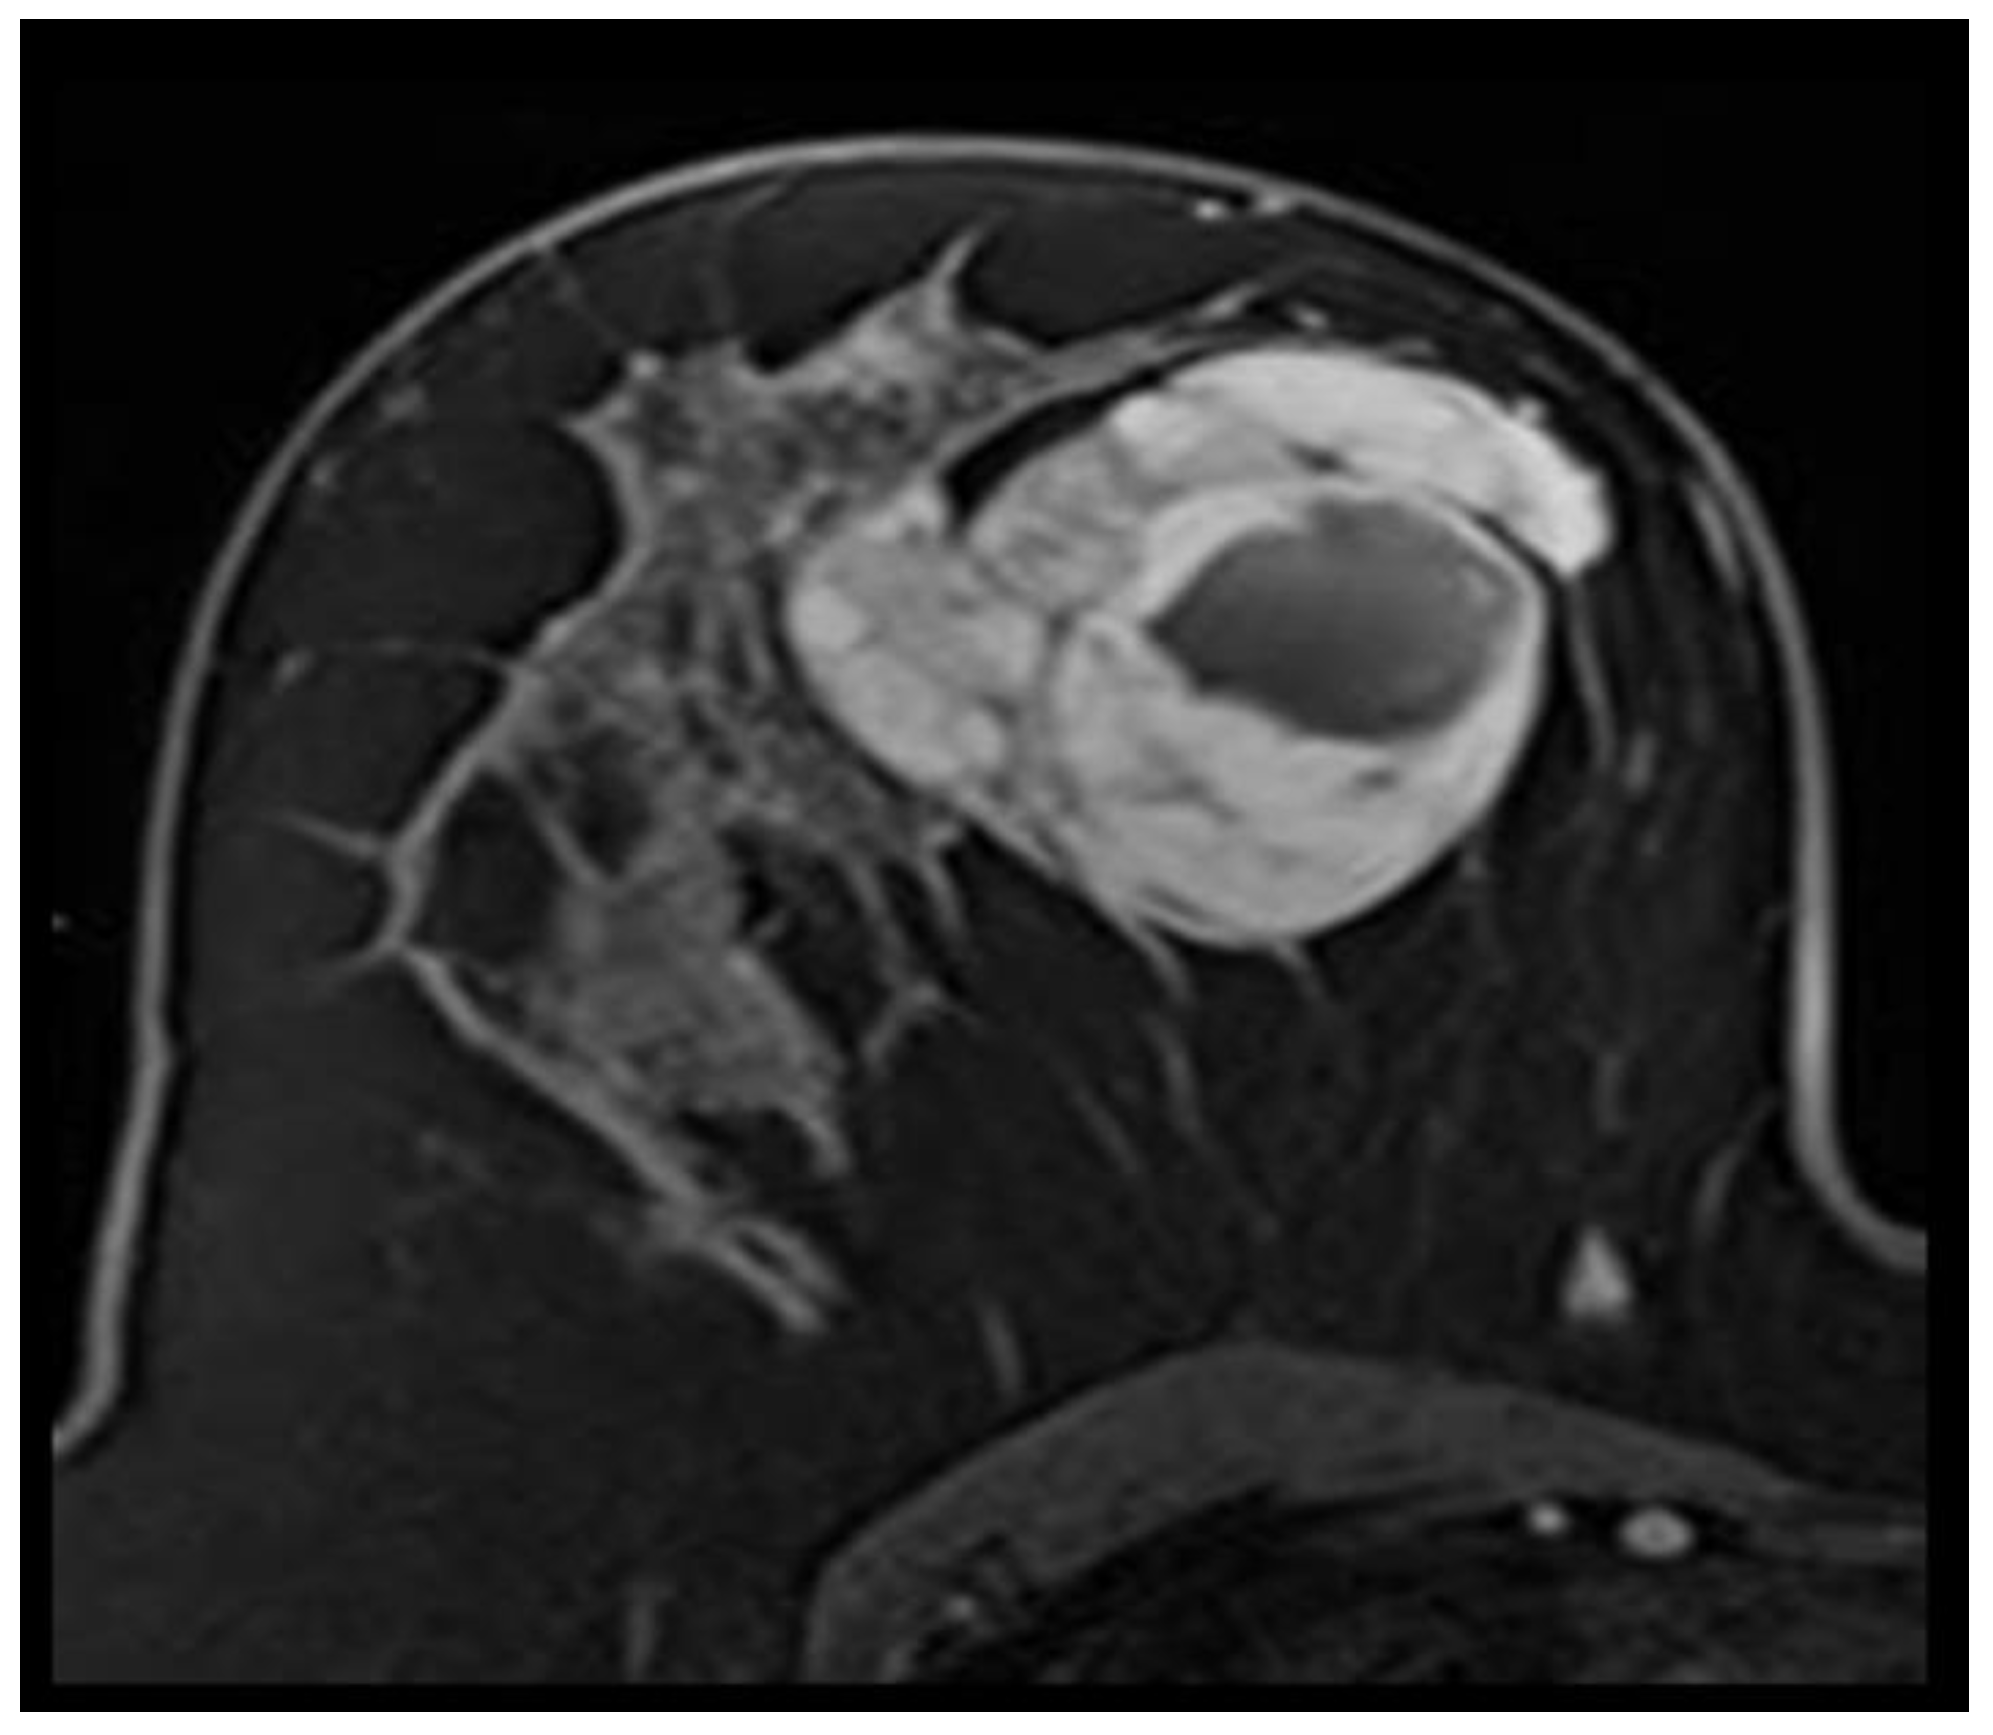

Phyllodes tumors